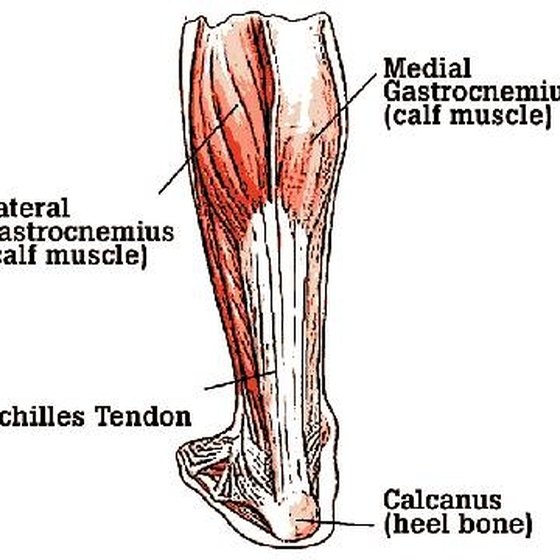

Achilles Tendon – Squat University

Achilles Tendon – NJSM

Achilles Heel, Achilles Tendon, Achilles Tendonitis Explained. Achilles …

Achilles Tendon Diagram – 1000+ images about medical anatomy on …